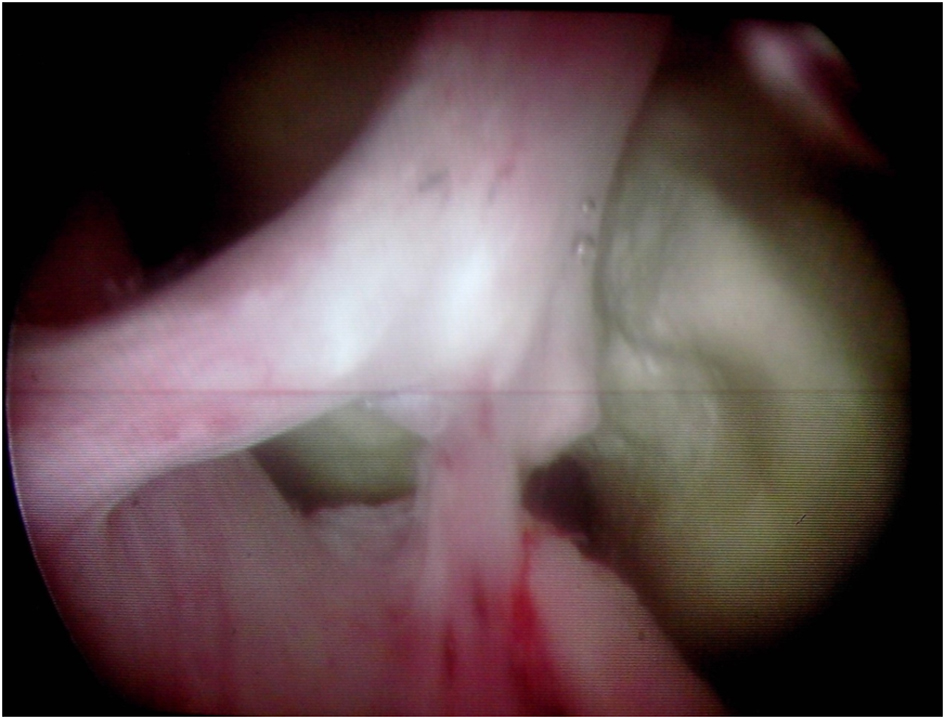

The patient was not compliant and presented again with LUTS, 2 years later. Retrograde cystography was performed and revealed recurrent 5 cm prostatic urethral calculus with a significant post void urine volume, large bladder neck and no evident urethral stenosis (Fig. 2). Complete blood count, renal function, serum parathyroid hormone, and serum calcium levels were within normal limits. An urethrocystoscopy showed normal urethra and a giant prostatic urethral calculus of uniform structure partially located in prostatic urethral diverticulum (Fig. 3). Because of the large stone burden, complete endoscopic removal was not feasible. Therefore, calculus was extracted entirely via cystotomy through bladder neck (Fig. 4). Postoperative plain radiography showed no residual calculus within the urinary tract. Infrared stone analysis revealed that it was composed of calcium phosphates.

![]() Click for large image | Figure 3. Urethroscopy: giant prostatic urethral calculus with prostate diverticulum. |